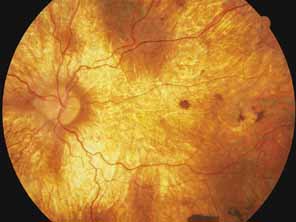

First described by Nettleship12 in 1884, central areolar choroidal dystrophy (CACD) (MIM No. 215500, Phenotype catalog number (MIM) from McKusick VA: Mendelian Inheritance in Man. Catalogs of Human Genes and Genetic Disorders. 12th ed. Baltimore: Johns Hopkins University Press, 1998 [http://www.ncbi.nlm.nih.gov/Omim/]), as it is most appropriately called,13 has been described under many names, including central areolar choroidal sclerosis, central areolar choroidal atrophy, central angiosclerosis, and central senile choroiditis.14,15 The disorder can be autosomal dominant or autosomal recessive, and phenocopies can occur from many other diseases, including mutations of peripherin/RDS16–19 and advanced stages of macular dystrophies (see later text). A locus for CACD has been identified on chromosome 17p.20 The earliest symptoms result from pericentral scotomas and include difficulty reading, poor dark adaptation, reduced visual acuity, and glare sensitivity. The earliest fundus findings are subtle and include pigment epithelial and choriocapillaris lesions in the macula (Fig. 1A) that enlarge and eventually form the punched-out central atrophic lesions typical of this disease (Fig. 1B). Histopathology shows fibrotic scarring with absence of choriocapillaris, retinal pigment epithelium, and overlying photoreceptors in the affected areas.21 The Ganzfeld electroretinogram is usually normal early in the course but may become mildly to moderately abnormal for cone and rod responses late in the course of disease when extensive atrophy of the choroid and secondarily the pigment epithelium and neurosensory retina occurs. Recent studies using the multifocal ERG have indicated that the abnormality of retinal function extends beyond the borders of the visible atrophy and is consistent with presynaptic photoreceptor dysfunction.22 The EOG can be normal or mildly abnormal depending on the extent of associated retinal pigment epithelial dysfunction.

Fig. 1 A. Right eye of a 22-year-old woman with central areolar choroidal dystrophy in early stage showing discrete, oval macular lesion. Visual acuity was 20/100. B. Left eye of a 57-year-old woman (mother of patient shown in A) with typical large depigmented atrophic macular lesion. Visual acuity was 20/300. (From Carr RE: Central areolar choroidal dystrophy. Arch Ophthalmol 73:32, 1965)

Other forms of central choroidal dystrophy exist that do not show the discrete oval lesions of typical central areolar choroidal sclerosis. These forms of central choroidal choriocapillaris atrophy often present with progressive pigment epithelial mottling and patchy choriocapillaris atrophy initially limited to the macula (Figs. 2A and 2B). With time, the atrophy enlarges and eventually encompasses the entire posterior pole (Fig. 2C). For this form of central choroidal atrophy, a gradual transition usually occurs from atrophic central pigment epithelium and choriocapillaris to essentially normal retina and choroid in the peripheral fundus.

Fig. 2 Central choroidal dystrophy of a less discrete form than central areolar choroidal dystrophy, showing in early stages the focal pigment epithelial and choriocapillaris defects in a male at 30 years of age (A) and the subsequent progression evident at 45 years of age (B). C. Late stage of central choroidal dystrophy showing atrophic macular choroid in a 54-year-old woman (mother of patient shown in A and B). The father of the patient shown in C was similarly affected, suggesting autosomal dominant inheritance.